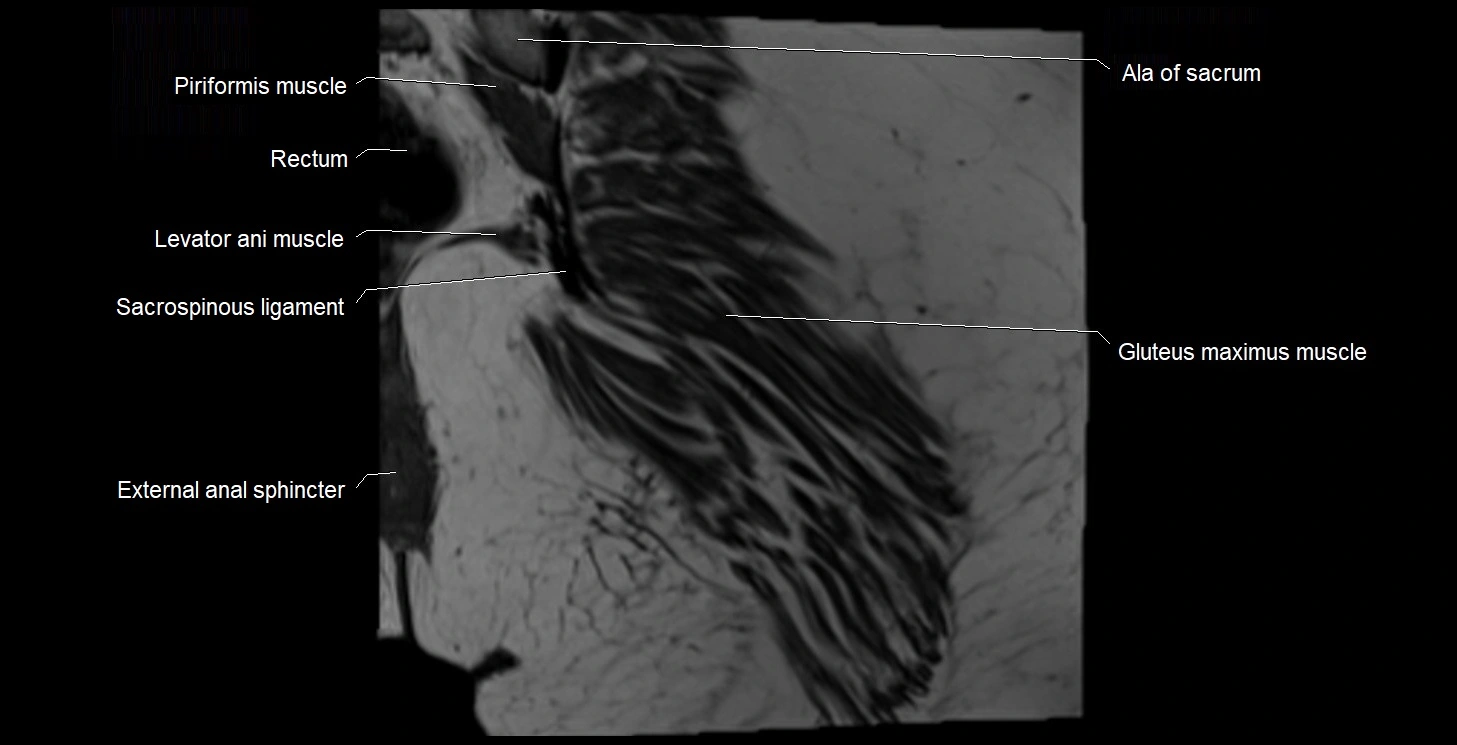

- Ala of sacrum

- External anal sphincter

- Gluteus maximus muscle

- Levator ani muscle

- Rectum

- Sacrospinous ligament